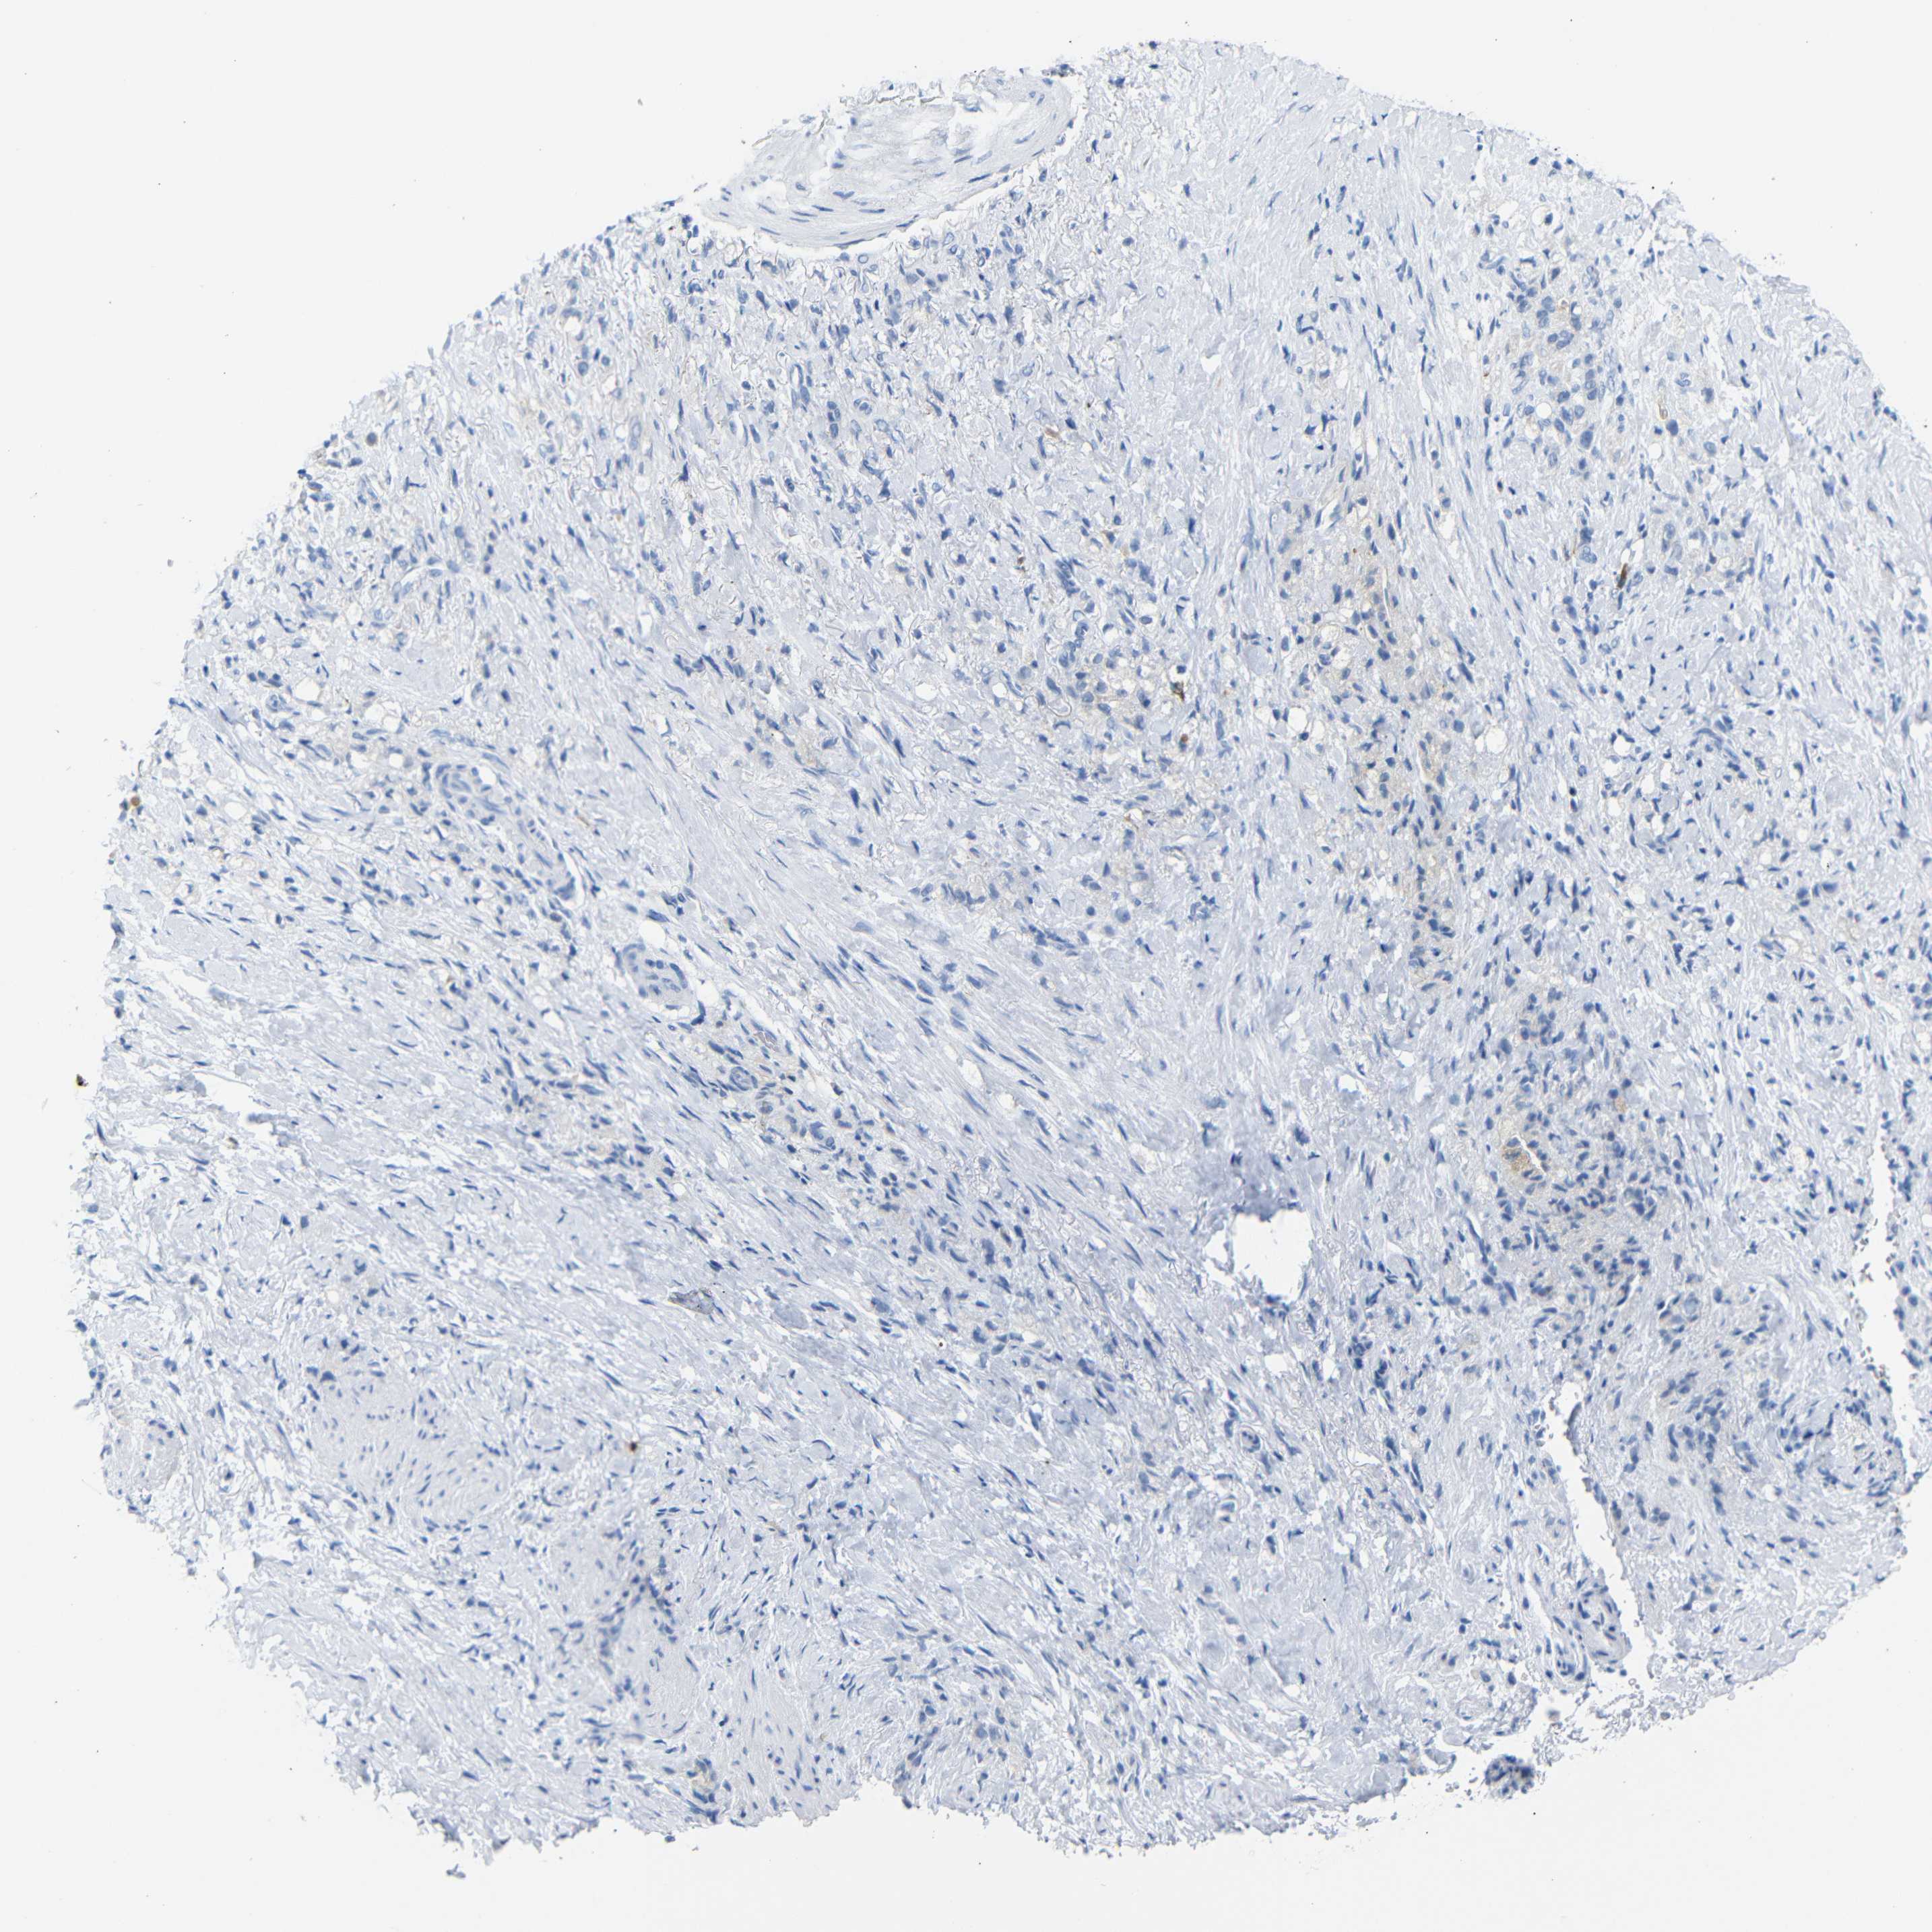

STOMACH CANCER - Protein expressioni

A mouse-over function shows sample information and annotation data. Click on an image to view it in a full screen mode. Samples can be filtered based on level of antibody staining by selecting one or several of the following categories: high, medium, low and not detected. The assay and annotation is described here.

Note that samples used for immunohistochemistry by the Human Protein Atlas do not correspond to samples in the TCGA dataset.

Antibody stainingi

Antibody staining in the annotated cell types in the current human tissue is reported as not detected, low, medium, or high, based on conventional immunohistochemistry profiling in selected tissues. This score is based on the combination of the staining intensity and fraction of stained cells.

Each image is clickable and will lead to virtual microscopy that enables deeper exploration of all samples and also displays staining intensity scores, fraction scores and subcellular localization as well as patient and tissue information for each sample.

Antibody HPA013323

Staining

High

Medium

Low

Not detected

Intensity

Strong

Moderate

Weak

Negative

Quantity

>75%

75%-25%

<25%

None

Location

Nuclear

Cytoplasmic/membranous

Cytoplasmic/membranous,nuclear

Adenocarcinoma, NOS

Adenocarcinoma, High grade